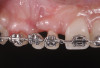

Fig 5. Start of orthodontic forced eruption to develop sites Nos. 6 and 8 before implant placement. A denture tooth was common-tied to the archwire to serve as a pontic. Anchorage requirements determined the extent of bracket placement.

Figure 5

Due to its predictability in achieving bone remodeling and developing alveolar ridge height while preserving or improving soft-tissue architecture, forced eruption was included as part of the interdisciplinary approach to treat the patient in the present case (Figure 5). Only stretching forces are applied to the periodontal ligament during the forced-eruption movement. This provides the stimulus for bone apposition within the socket walls. Generally, the orthodontic movement should be controlled so the root is extruded without impinging on the socket walls. In the presence of periodontal health, bone apposition and gingival remodeling will result in coronal proliferation of the attachment apparatus.29,30